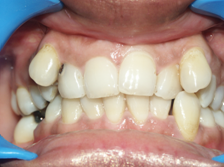

Irregular Teeth

Correction of Crowding

Teeth which are irregular can be straightened by Orthodontic treatment which if severe might require removal of teeth.